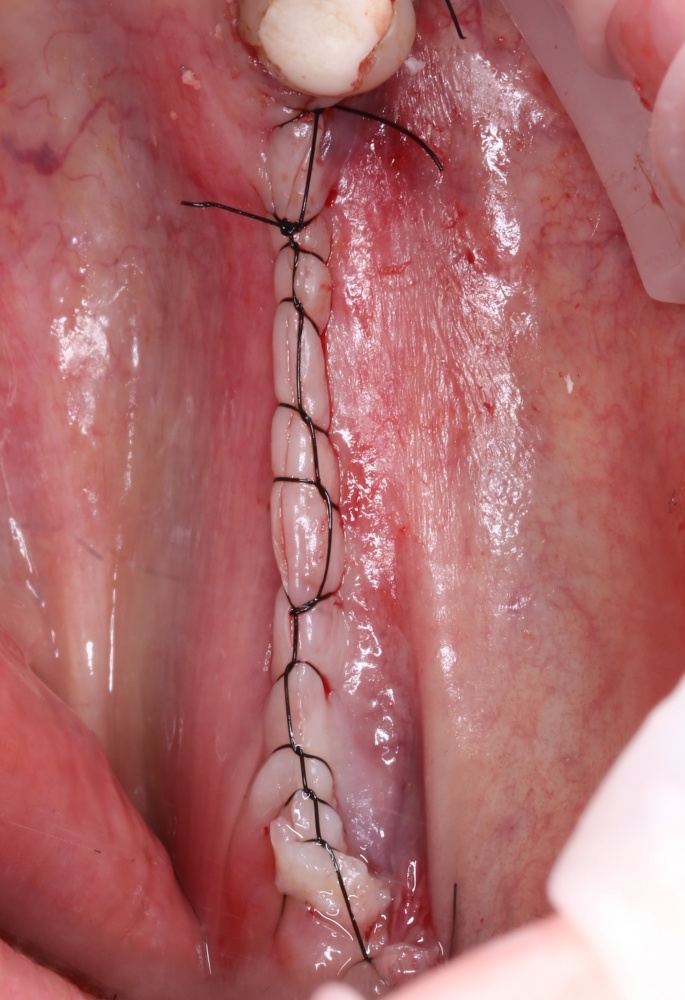

Осталось только наложить швы:

и подождать 3-4 месяца до интеграции имплантов.